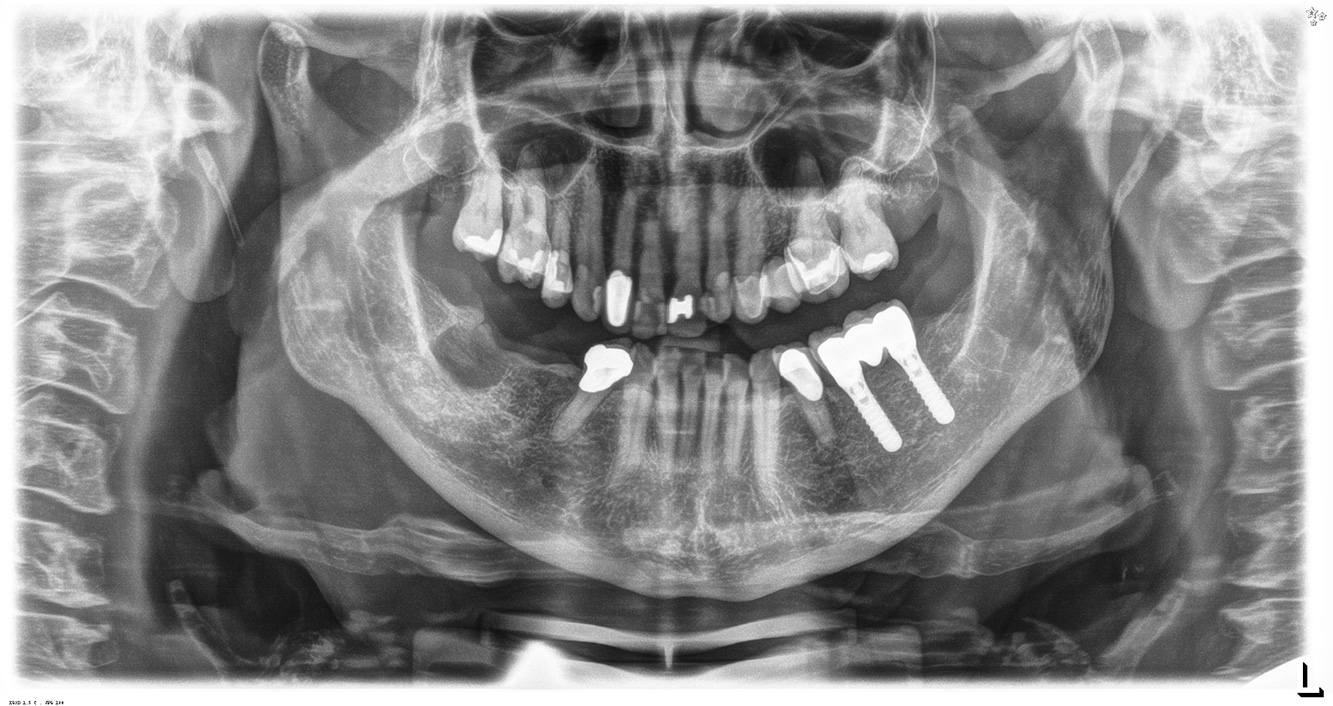

La paciente de 68 años no tiene enfermedades previas relevantes de la salud general ni toma medicación; sus hábitos alimentarios tampoco suponen un riesgo especial. La paciente tiene dos implantes (tercer cuadrante, desde hace cinco años) y una enfermedad previa periodontal (periodontitis en etapa IV, grado B) con pérdida dental. Actualmente las condiciones periodontales son estables, pero la periodontitis aumenta de manera determinante las complicaciones biológicas cuando se realizan implantes y puede ocasionar la pérdida de un implante (21). Para la sesión de profilaxis se hacen cuatro recomendaciones.

Debido a la situación del implante con la enfermedad periodontal previa, la paciente tiene riesgo de desarrollar periimplantitis; se recomienda un intervalo de recuperación de tres a cuatro meses.